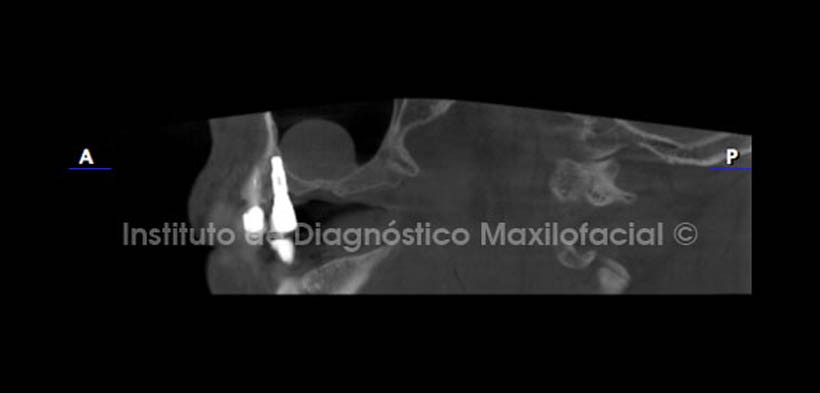

Los cortes axial, coronal y sagital; confirman la apreciación diagnóstica mencionada anteriormente ya que se evidencia la inmersión de la entidad en el seno maxilar y la relación estrecha que tiene con la pared basal; relación que es característica del Quiste Mucoso de Retención (Fig. 4, 5 y 6).

Así mismo, en los cortes coronal y transaxiales a nivel de las regiones de las piezas 17 y 16, se aprecia la neumatización alveolar del seno con marcada proximidad a la cima del reborde alveolar (Fig. 8 y 9).